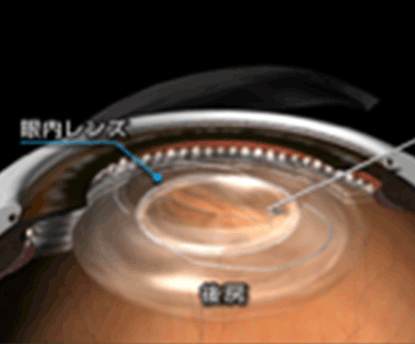

白内障手術では、水晶体を乳化させて吸引して取り除き、目の中に人工のレンズを挿入します。これが「眼内レンズ」です。その為、『白内障手術』は同時に『屈折矯正手術』でもあることになります。近視が強かったり、乱視が強かったり、老眼で困っていたりする患者様は白内障手術の際に、ライフスタイルにあった快適な生活を送れる屈折矯正手術を同時にうける事ができる事になります。

眼内レンズは、白内障の手術後、水晶体の代わりになるもので、若い頃の水晶体と同等の役割を果たすことが理想です。もちろん人工のレンズですから、水晶体が持つすべての機能に取って代われるものではありませんが、近年、この領域の技術は目覚ましい進歩を遂げており、単に濁りを取るだけでなく、より質の高い見え方を達成できるような付加価値がついた眼内レンズが実用されています。老眼矯正白内障手術・乱視矯正白内障手術を参考にして下さい。

切開創を拡げることなく、眼内レンズを小さく折りたたんでインジェクターを用いて、眼内レンズを眼内にインサートします。これで白内障手術は終了です。

下記リンクより眼内レンズの詳しいご案内を参考にして下さい。満足度のある白内障手術を受けて頂くために、手術法だけでなく、眼内レンズについてきちんと知っておくことが大切です。近年、この領域の技術は目覚ましい進歩を遂げており、単に濁りを取るだけでなく、より質の高い見え方を達成できるような付加価値がついた眼内レンズが実用されています。

- 残した嚢を利用して眼内レンズを折りたたんで挿入します。

眼内レンズは、嚢で固定され、小切開部分も縫合を行わず自己閉鎖します。